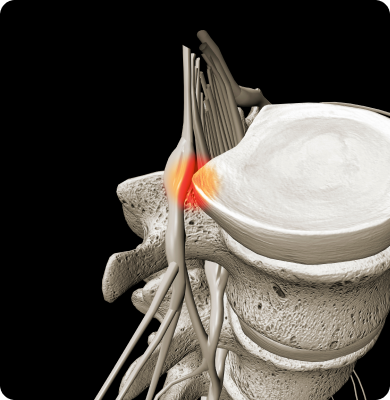

경추 사이의 디스크가 탈출하여 신경을 압박하는 질환

일상생활의 잘못된 습관이나 사고 등으로 인해 목에 직접적인 충격이 가해졌을 때 나타나기 쉽습니다.일상생활의 잘못된 습관이나 사고 등으로 인해 목에 직접적인 충격이 가해졌을 때 나타나기 쉽습니다.